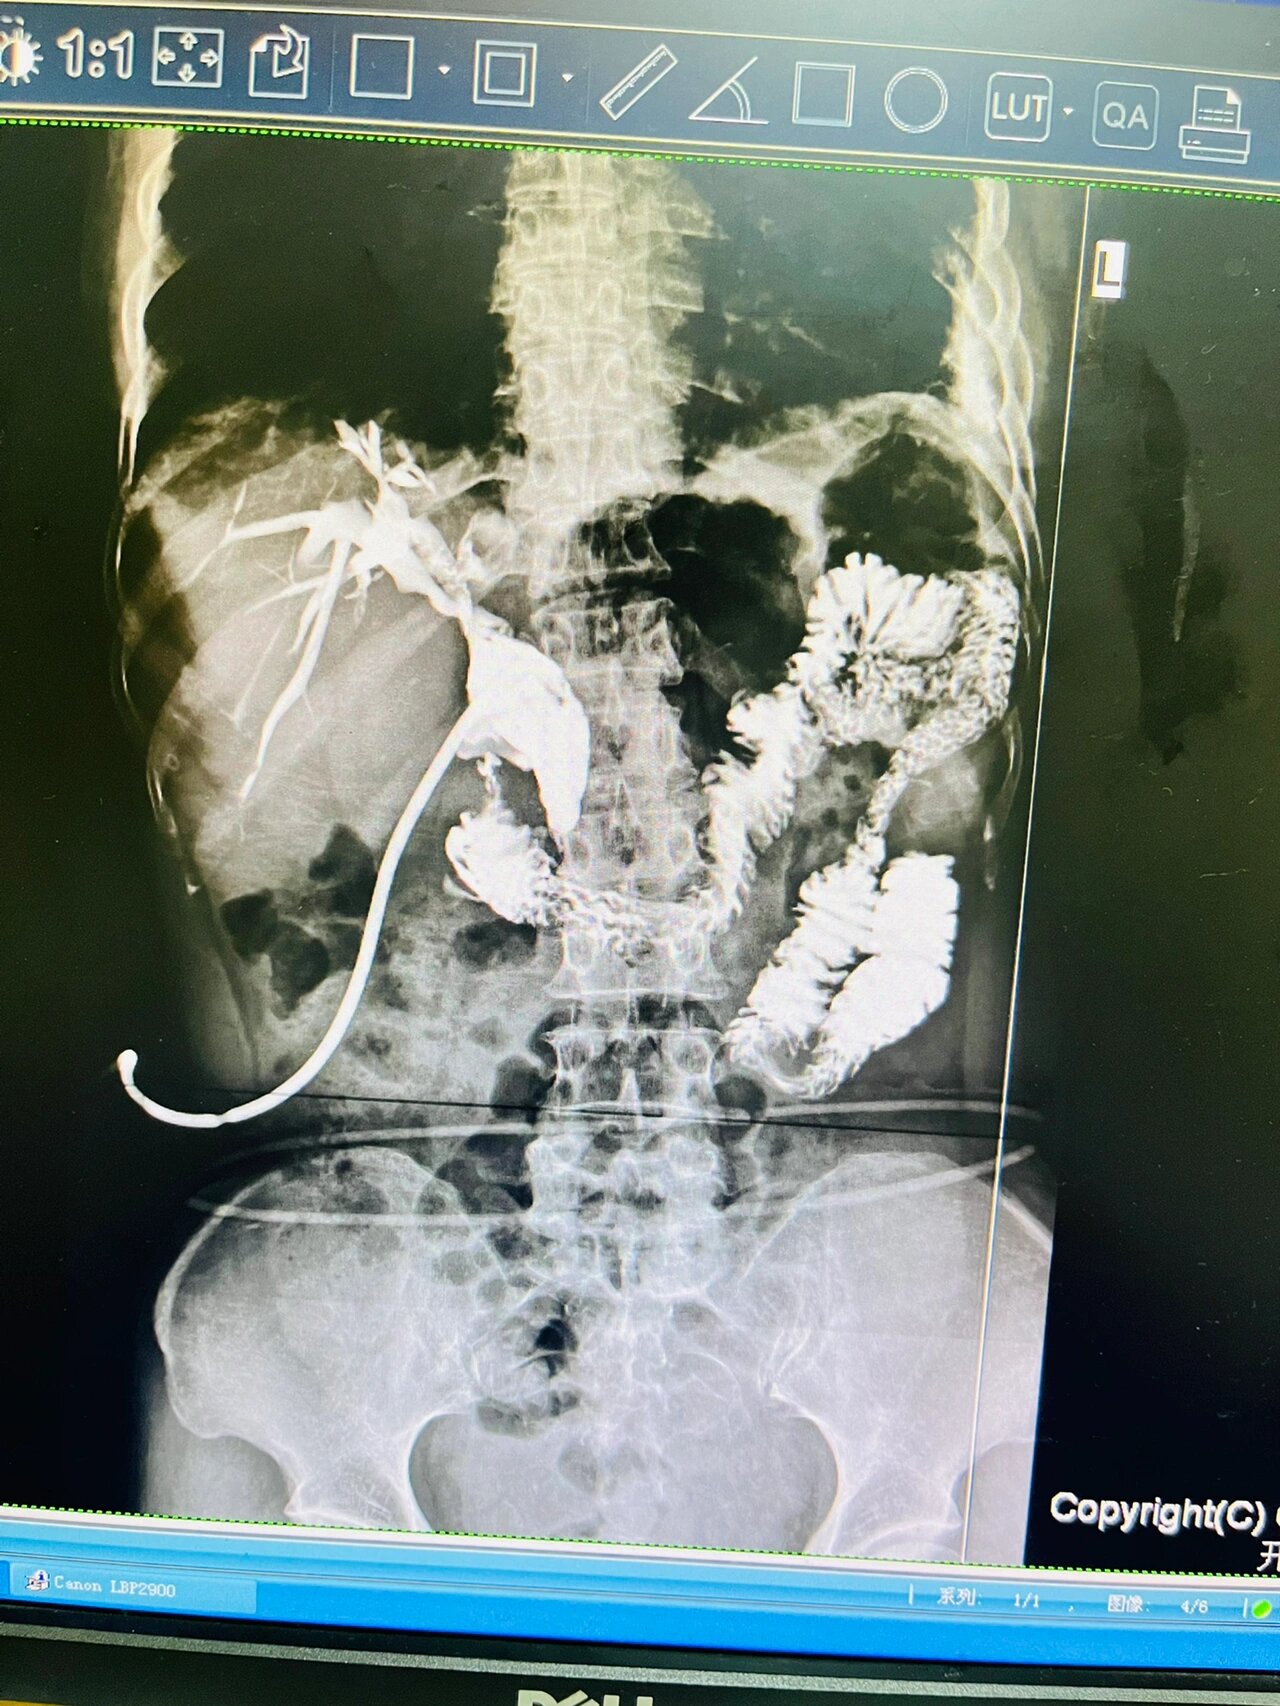

t管引流术后造影片子,求助诊断结果

求解图--t管造影